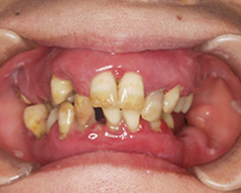

口の中全体の歯茎が腫れ上がっており、ほとんど物がかめないということで来院されました。

写真(1) 全体的に歯肉がはれている、歯ブラシをすると血と膿が出ていて口臭もする

治療前

全体に歯茎が腫れ上がってしまい歯が動いて、噛み合わせが大きく崩れている。